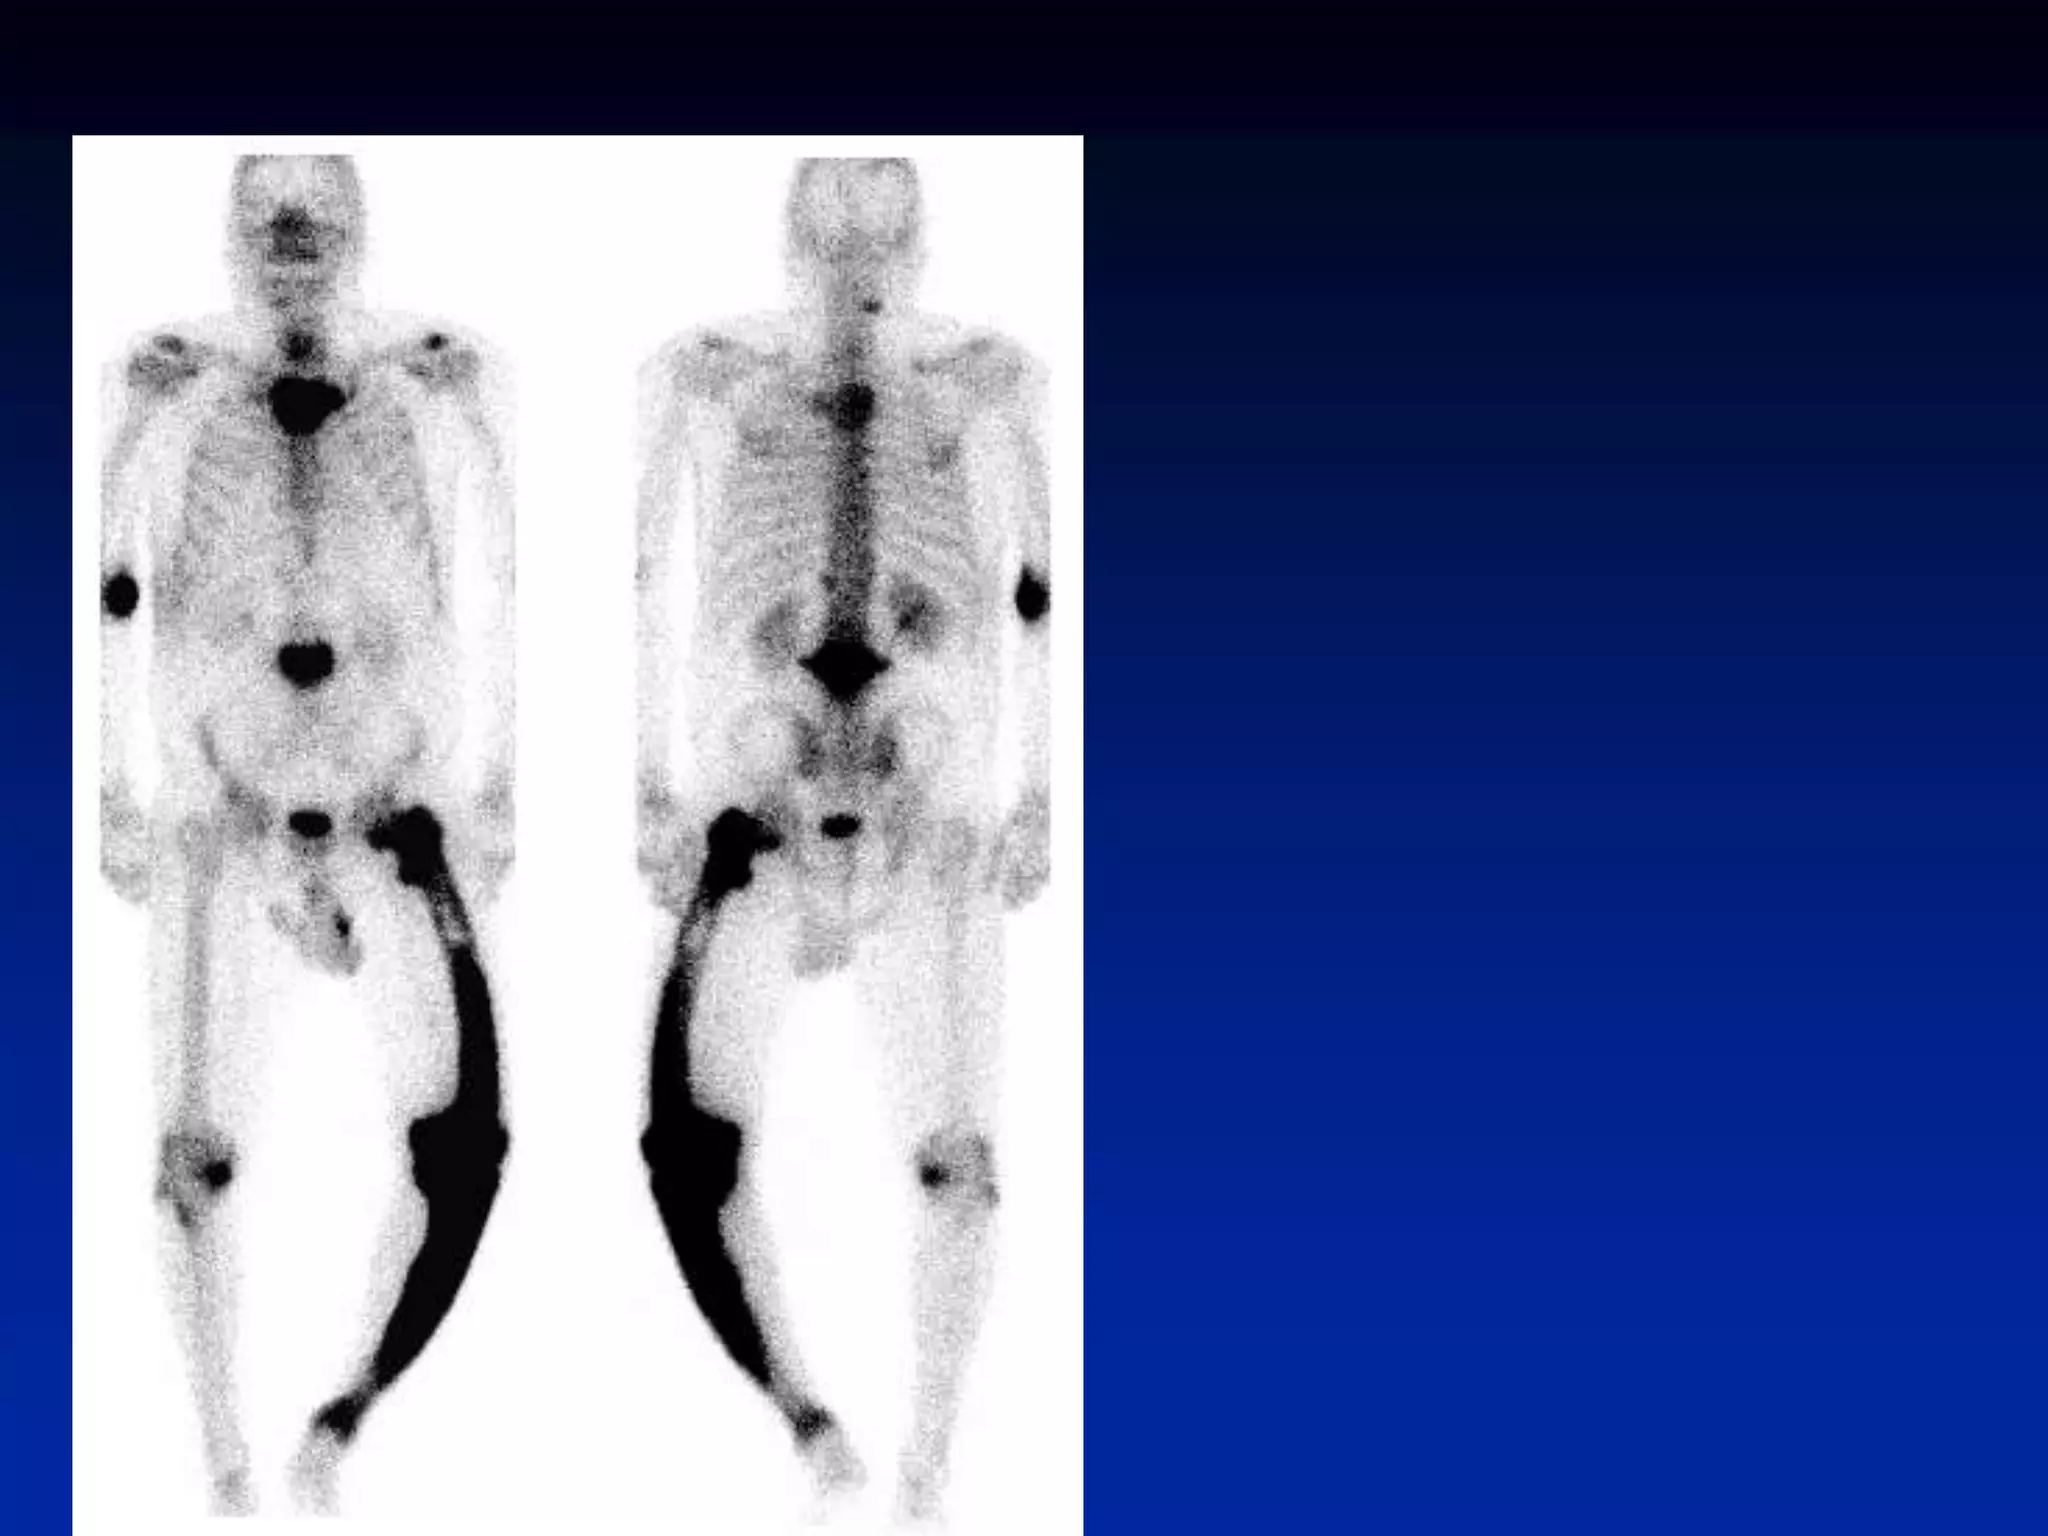

Superscan

• When the metastatic process is

diffuse, virtually all of the radiotracer

is concentrated in the skeleton, with

little or no activity in the soft tissues or

urinary tract. The resulting pattern,

which is characterized by excellent

bone detail, is frequently referred to as

a superscan

• A superscan may also be associated

with metabolic bone disease. Unlike in

metastatic disease, however, the

uptake in metabolic bone disease is

more uniform in appearance and

extends into the distal appendicular

skeleton.

Superscan • When themetastatic process is diffuse, virtually all of the radiotracer is concentrated in the skeleton, with little or no activity in the soft tissues or urinary tract. The resulting pattern, which is characterized by excellent bone detail, is frequently referred to as a superscan • A superscan may also be associated with metabolic bone disease. Unlike in metastatic disease, however, the uptake in metabolic bone disease is more uniform in appearance and extends into the distal appendicular skeleton.